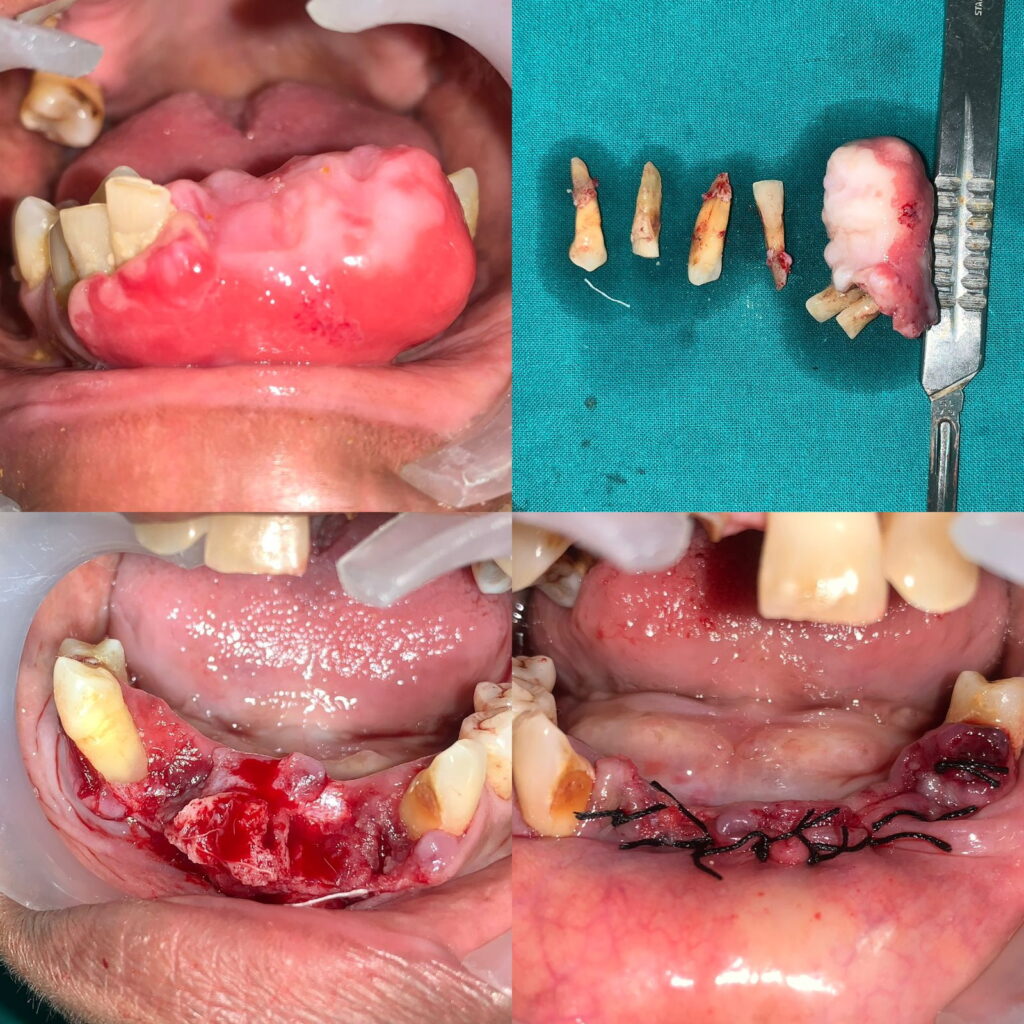

Case of cemento ossifying fibroma (Excisional biopsy)